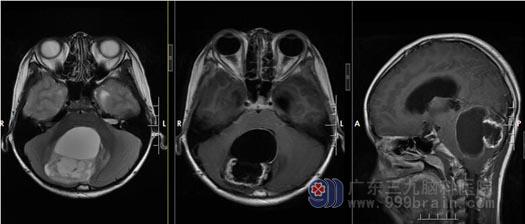

小锐的病情危重,入院后第一天就进行了相关的术前准备, 术前MRI 检查:小脑半球巨大囊实性肿瘤, 考虑高级别恶性肿瘤可能,合并梗阻性脑积水。

制定了详细的手术方案后,由鲁明副院长主刀将小锐的肿瘤在显微镜下全切除,术后复查MRI显示:原小脑半球巨大囊实性肿瘤已全切除,脑积水亦明显缓解。